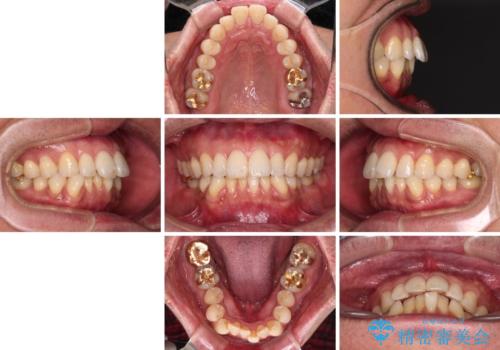

- 口元の突出感を気にして来院された患者様です。

強い咬合力と上顎前歯の傾斜により前歯が突出し、唇が閉じにくい状況であったため、上下左右の第一小臼歯4本を抜歯し、ワイヤー装置にて矯正治療を行うこととしました。

非常に咬合力が強いため、抜歯したスペースが閉じるのか不安でしたが、順調に歯が移動し、予定よりも早く治療を終えることができました。